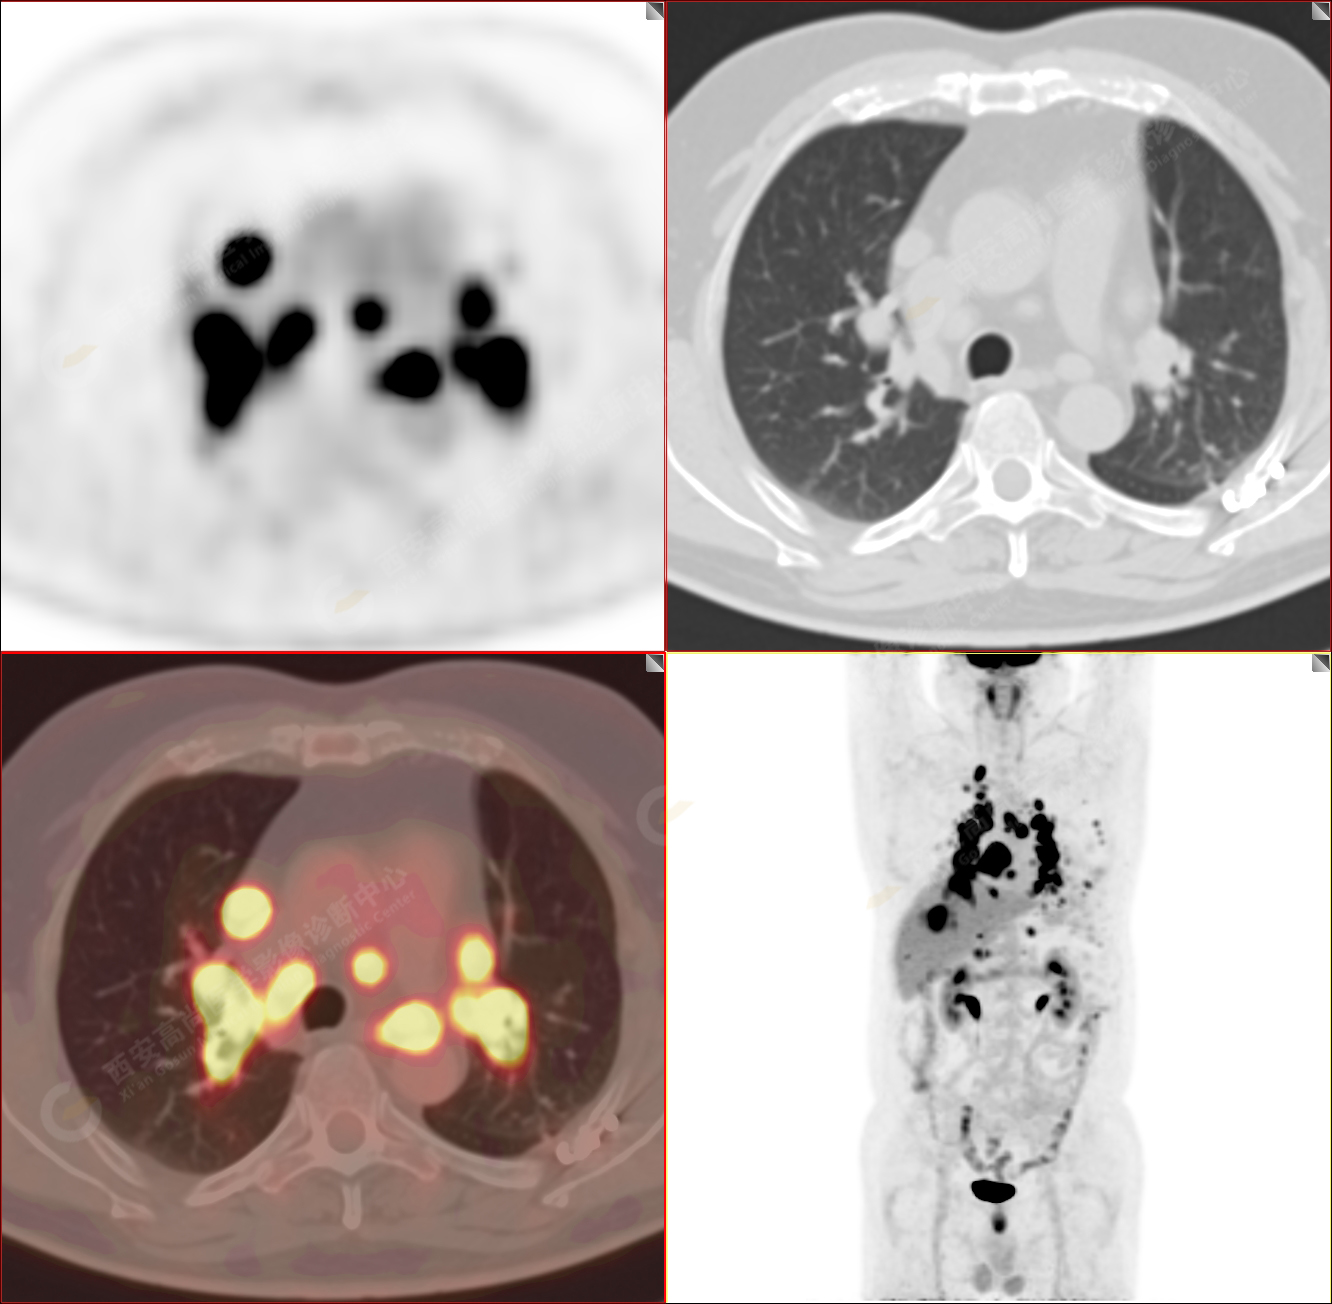

男性,53歲,頭暈半月入院,CT發(fā)現(xiàn)肺內(nèi)腫塊,雙肺多發(fā)大小不等實(shí)性及粟粒樣結(jié)節(jié),雙肺門(mén)及縱隔多發(fā)腫大淋巴結(jié)。病程中無(wú)發(fā)熱、胸悶氣及胸部不適。既往:左側(cè)肋骨外傷史。

PET/CT圖像